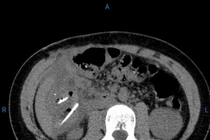

Khi vào Khoa Cấp cứu A9 - Bệnh viện 19-8, bệnh nhân tỉnh, tiếp xúc tốt, có xây xát vùng gò má và hai bàn tay, đau ngực trái, mạch và huyết áp ổn định. Khám cận lâm sàng ghi nhận gãy xương sườn 4, 5, 7 bên trái; gãy rạn cung tiếp gò má trái và gãy thành trước xoang hàm trái. Siêu âm bụng chưa phát hiện tổn thương.